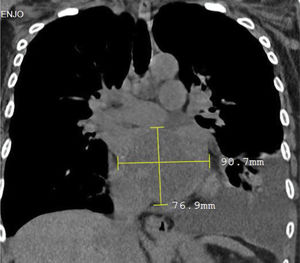

Derrame pleural recidiva siendo necesaria la realización de toracocentesis evacuatorias hasta en 4 oportunidades. Durante el estudio etiológico del derrame pleural se realiza biopsia pleural con resultado negativo para malignidad; tomografía torácica donde se evidencia la presencia de masa intracardíaca izquierda asociada a derrame pleural (fig. 1). La ecocardiografía confirma dicho hallazgo: tumor gigante en la aurícula izquierda que protruye hacia el ventrículo izquierdo; función sistólica biventricular conservada e hipertensión pulmonar poscapilar severa (fig. 2).

La paciente fue sometida a cirugía cardíaca con circulación extracorpórea mediante esternotomía media. Se realizó canulación aorto bi-cava, con bypass cardiopulmonar total. Abordaje por auriculotomía izquierda, hallando tumoración de aspecto mixomatoso, pediculada, adherida a la pared posterior de la aurícula izquierda, de diámetro aproximado de 8×7cm, de consistencia blanda, la cual fue removida en su totalidad (fig. 3). Tiempo de circulación extracorpórea: 1hora 30min, tiempo de pinzamiento aórtico: 45min. La ecocardiografía transesofágica intraoperatoria no reporta insuficiencia mitral residual.